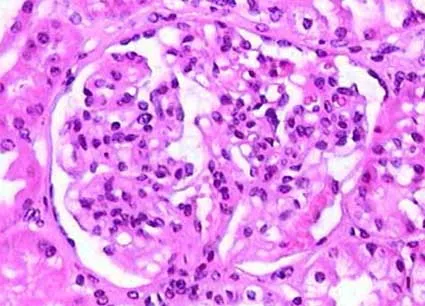

Meu paciente com NIgA tem proteinúria entre 0,5–1,0 g/dia, já está em iECA e iSGLT2: devo pensar em imunossupressão?

Proteinúria entre 0,5–1,0 g/dia na NIgA não é benigna e já se associa a maior risco de progressão renal. A evidência atual reforça <0,5 g/dia como alvo terapêutico, valorizando proteinúria cumulativa e tendência ao longo do tempo. Antes de pensar em imunossupressão, o foco deve ser otimização máxima da terapia de suporte e estratificação cuidadosa de risco.